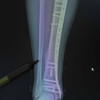

Trafikte motosikletlerin sayısı her geçen gün artıyor, ancak bu artış kazalar ve yaralanmalarda da belirgin bir yükselişi beraberinde getiriyor. Medipol Üniversitesi Pendik Hastanesi’nden Ortopedi ve Travmatoloji Uzmanı Dr. Öğr. Üyesi Mehmet Soyarslan, motosiklet kazalarının çoğunda kırık ve yumuşak doku hasarlarının görüldüğünü belirterek, “Eğitimsizlik, koruyucu ekipman eksikliği ve bilinçsiz kullanım, en büyük tehlike kaynağı. Acile başvuran motosiklet kazalarının yaklaşık yarısında kas iskelet sistemi hasarı, bu olguların da yüzde 30-40’ında kırıklar görülüyor” uyarısında bulundu.

Türkiye’de trafiğe kayıtlı 6,5 milyondan fazla motosiklet bulunduğunu vurgulan Dr. Soyarslan, “Bazı illerde, motosiklet sayısı artık otomobil sayısını geçmiş durumda. Pandemidöneminde hızla büyüyen kurye sektörü bu artışta büyük rol oynadı. Büyük şehirlerde ise trafik ve park sorunundan kaçmak için bireysel kullanım yaygınlaştı. Eskiden acillerde düşme ya da araç çarpışması nedeniyle yaralanmaları görürdük, şimdi motosiklet kazaları açık ara önde. Bu kazalar sadece kırıklarla değil, kafa, göğüs ve karın travmalarıyla da karşımıza çıkıyor” dedi.